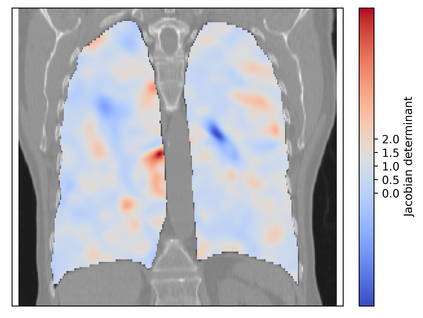

Deformable image registration is a fundamental task in medical image analysis and plays a crucial role in a wide range of clinical applications. Recently, deep learning-based approaches have been widely studied for deformable medical image registration and achieved promising results. However, existing deep learning image registration techniques do not theoretically guarantee topology-preserving transformations. This is a key property to preserve anatomical structures and achieve plausible transformations that can be used in real clinical settings. We propose a novel framework for deformable image registration. Firstly, we introduce a novel regulariser based on conformal-invariant properties in a nonlinear elasticity setting. Our regulariser enforces the deformation field to be smooth, invertible and orientation-preserving. More importantly, we strictly guarantee topology preservation yielding to a clinical meaningful registration. Secondly, we boost the performance of our regulariser through coordinate MLPs, where one can view the to-be-registered images as continuously differentiable entities. We demonstrate, through numerical and visual experiments, that our framework is able to outperform current techniques for image registration.